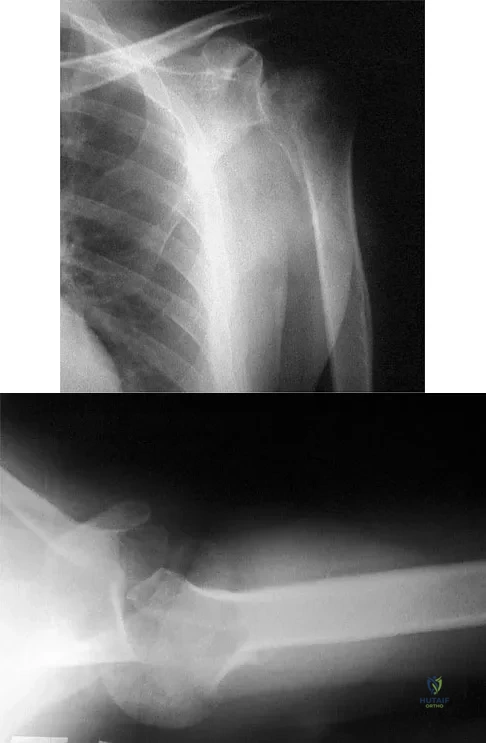

Question 70

A 50-year-old electrician who is right-hand dominant has had right shoulder pain and stiffness after sustaining an electric shock 2 months ago. An AP radiograph obtained at the time of injury was considered negative, and the patient was diagnosed with a shoulder sprain. The patient now reports continued shoulder pain and restricted motion. AP and axillary radiographs and a CT scan are shown in Figures 41a through 41c. Management should consist of

Explanation